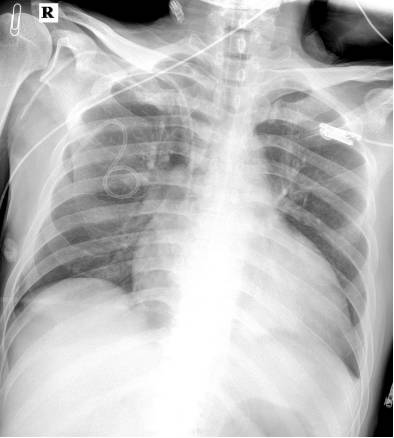

25日 17:00 呼吸平稳,拔除气管插管

序贯无创呼吸机辅助呼吸

逐渐减量:多巴胺、去甲肾上腺素、多巴酚丁胺